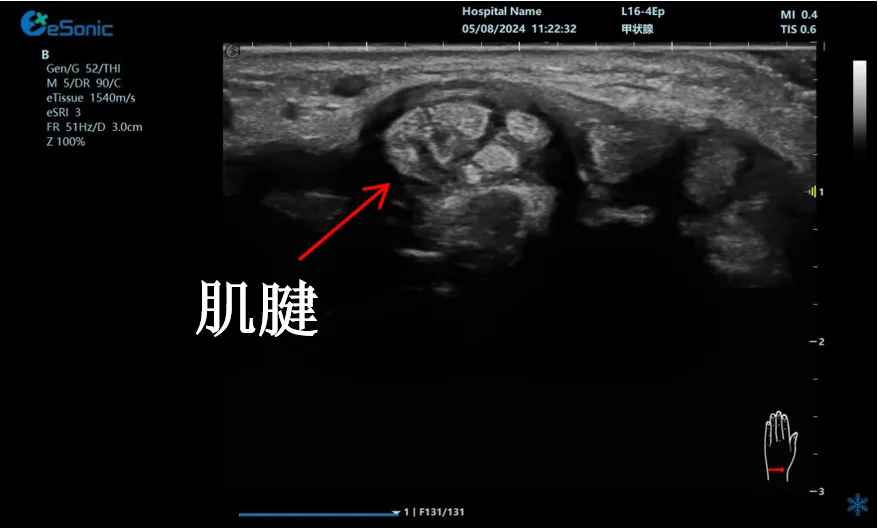

mFlow?技术在腱鞘炎诊疗中的应用

【背景】:左手腕关节第四腔室腱鞘炎。

【痛点】:普通彩色多普勒不敏感,只能看到细小点状血流,容易被忽略,难以进行分级诊断和疗效评估。

【方案】:3377体育医疗(ESI)超微血流技术可以看到腔室内肌腱周围环状血流,可充分提示:

1、处于炎症活动期;

2、根据血流进行分级诊断提示1级;

3、治疗后根据血流多少评估疗效(见右下图:治疗10天后复查超声,微血流图像血供消失)。